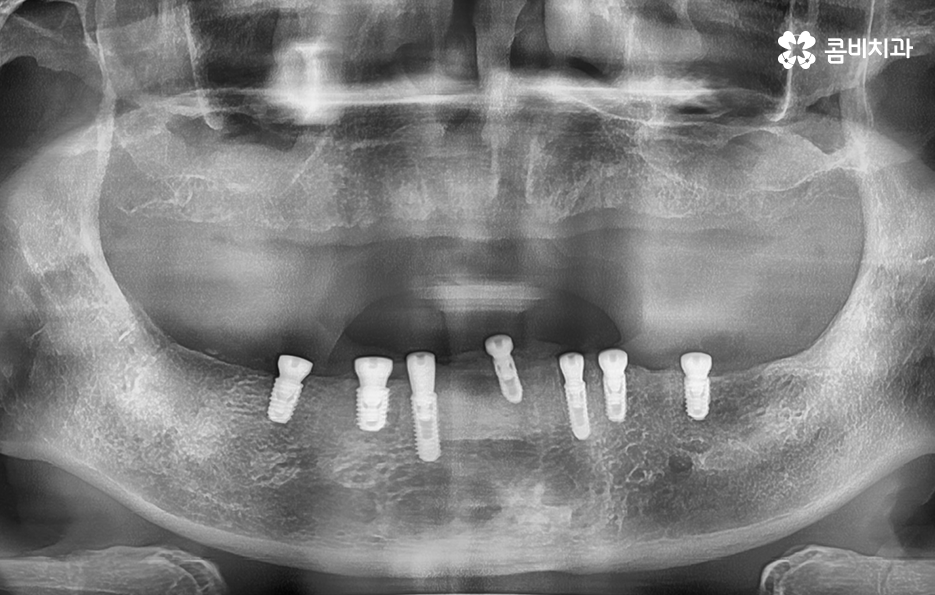

하지만 노년층의 환자분들의 경우 경제적인 부분이 부담스럽거나 치아를 잃은 개수만큼 임플란트를 식립하고 싶어도 잇몸 상태가 너무 좋지 않은 경우에는 임플란트 식립을 해야 하는 개수를 줄이고 치아의 머리부분을 연결하는 브릿지 형태로 임플란트 시술을 진행하는 경우가 있는데요

전체임플란트 해야 하는 상황에서 가장 권장하는 방법은 치아를 잃은 개수만큼 임플란트를 식립하는 방법이 되겠지만 그다음으로 잇몸 상태나 경제적 상황 등을 고려할 때 선택할 수 있는 방법 중 하나는 임플란트 브릿지를 활용한 치료 방법이라 할 수 있어요

임플란트 브릿지를 활용하여 전체임플란트를 하는 경우 보통 임플란트를 6~8개 정도 식립을 한 후에 임플란트의 머리부분을 연결하여 힘을 분산시키는 방법으로 저작력을 유지시키고 있어요